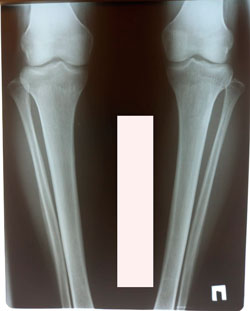

Исходник - 35 лет.

Дата операции - 15.01.2021

Вложения

image-18-01-21-09-59-4.jpg

image-18-01-21-09-59-1.jpg